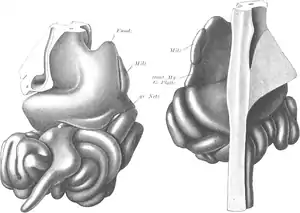

Pernkopf instructed them to paint the organs they saw in as much detail as possible, to make them look like living tissue in print. This was enabled by a special treatment of the paper used for watercolor images that allowed greater detail than that type of paint normally did. The only deviation from this high level of realism was the use of color, where Pernkopf instructed them to use brighter hues than those found in real cadavers so that a reader would better learn to recognize and distinguish key anatomical landmarks.[2]

Like Pernkopf, the four artists were also members of the Nazi Party and committed to its goals. They signaled this through the use of Nazi symbols in their work for the atlas. In his signature, Lepier frequently used the "r" at the end of his name as the basis for a swastika, and Endtrasser likewise used two Sig runes, the lightning-bolt insignia of the Schutzstaffel (SS), for the "ss" in his name. For illustrations he made in 1944, Batke similarly dated them by stylizing the two "4"'s as Sig Runes.[7]

The first volume of the atlas was published in 1937. It was large enough that it required two books, one devoted to anatomy in general and the other covering more specifically the chest and pectoral limbs. Four years later, in 1941, the second volume, likewise requiring two books, came out. It covered the abdomen, pelvis and pelvic limbs.[2]